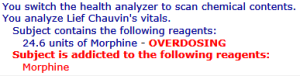

Используется для: Определение степени повреждения пациента

Стратегия: Используйте его на своем пациенте и посмотрите показания.